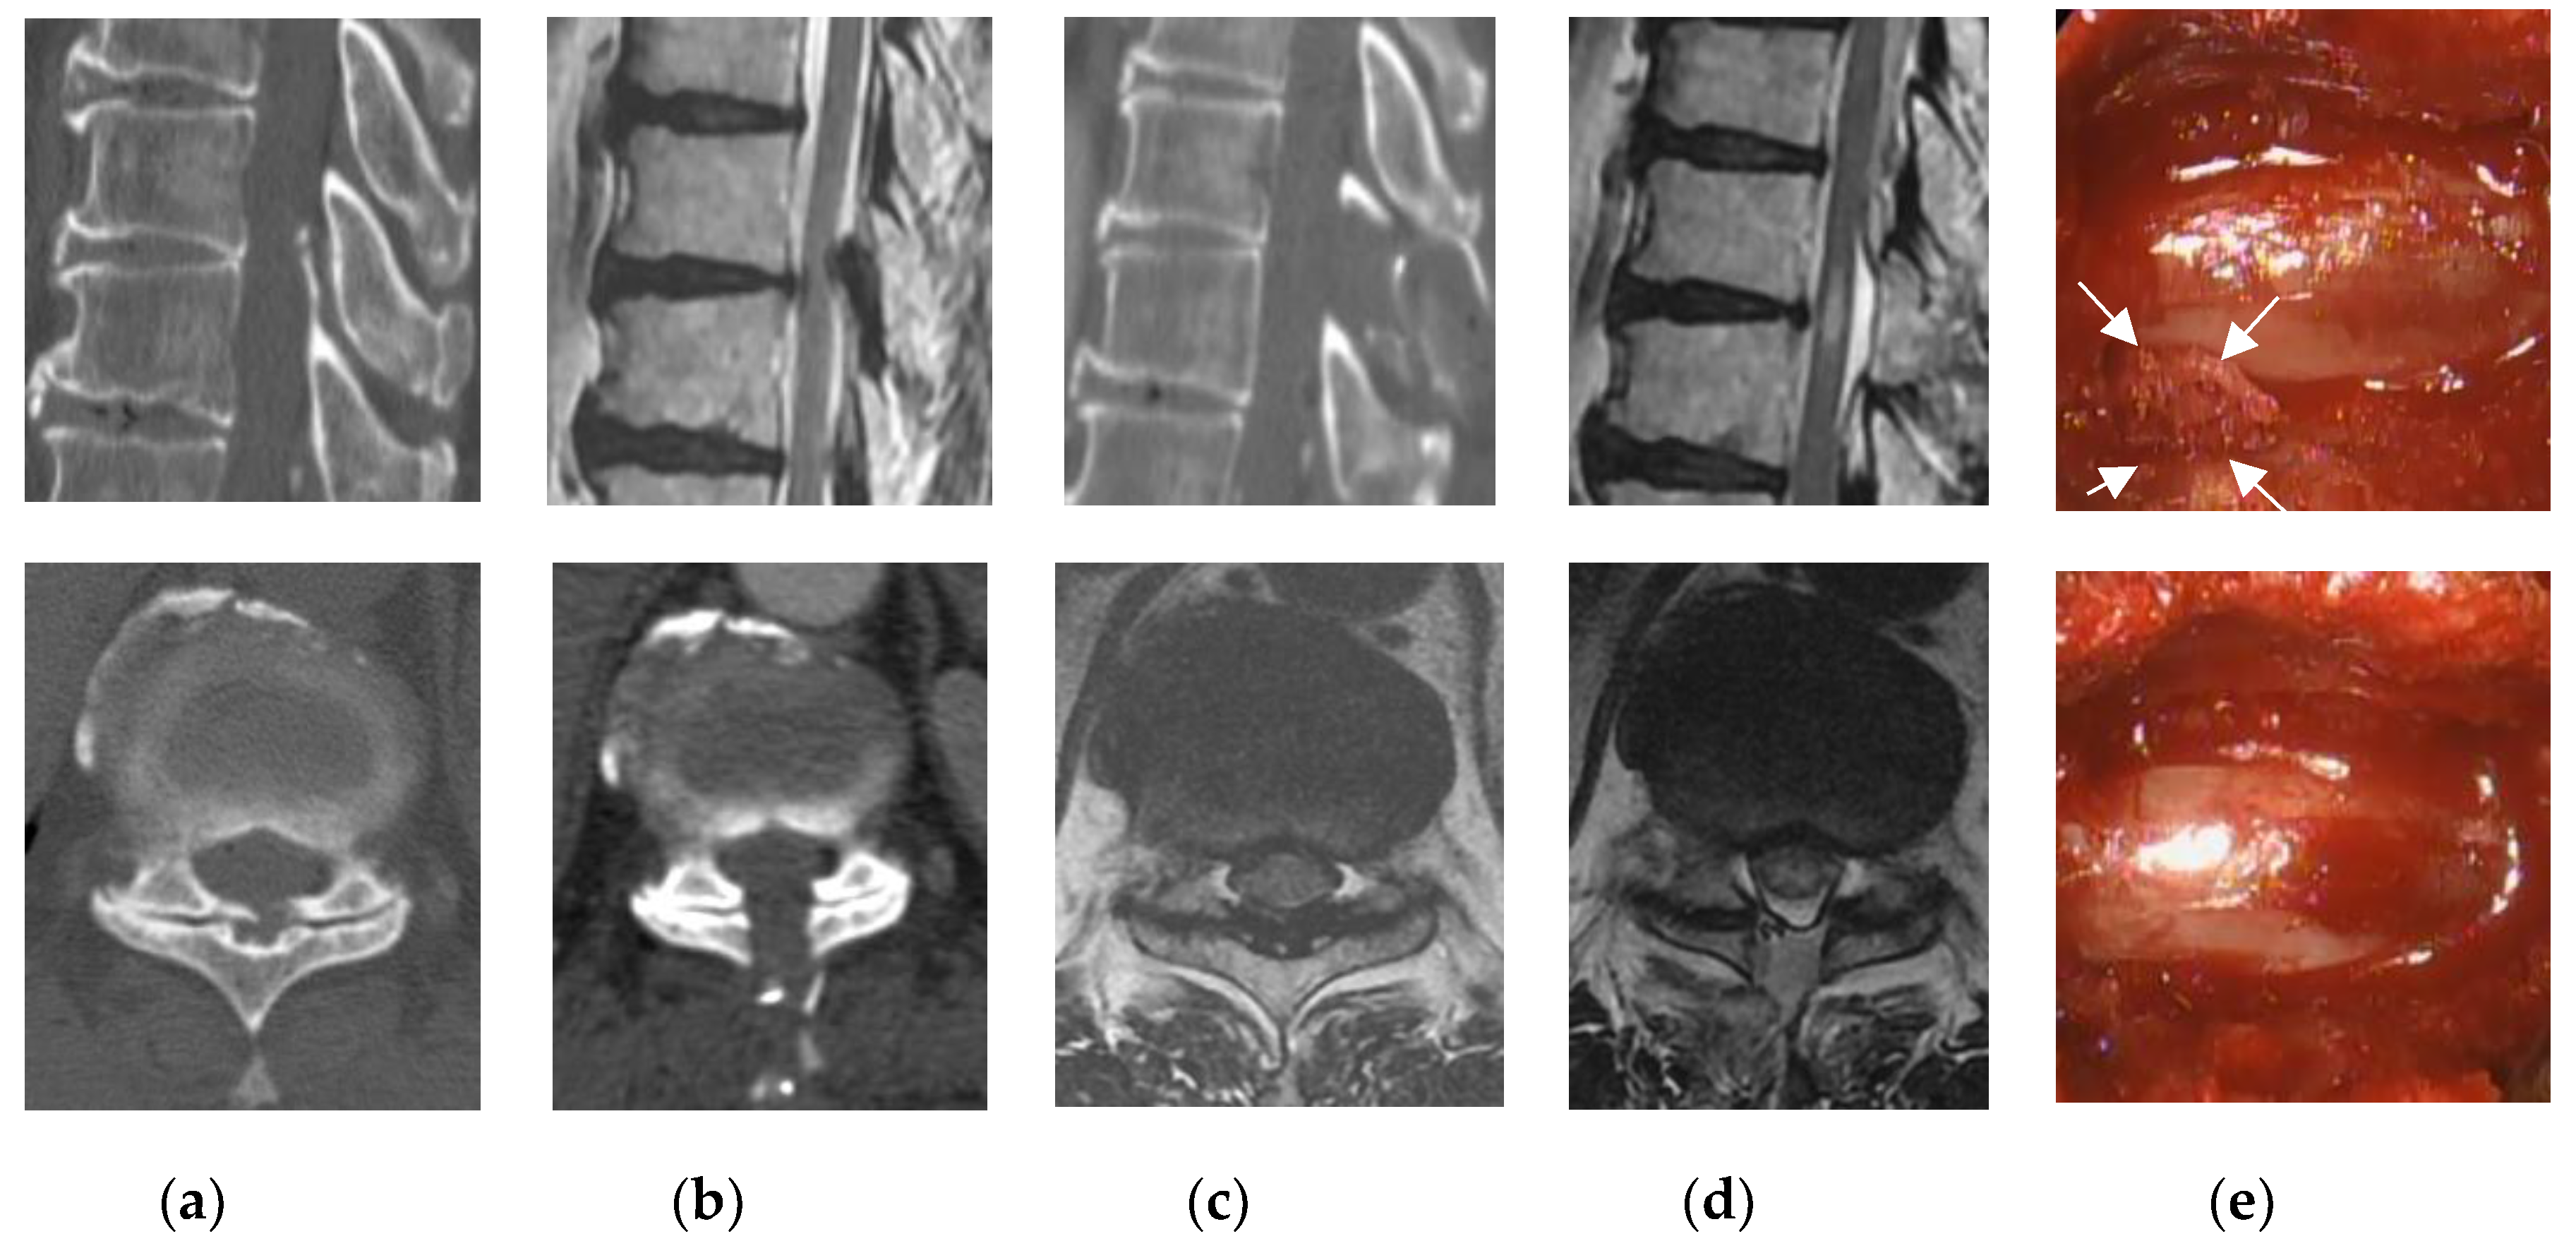

2.2. Surgical Technique